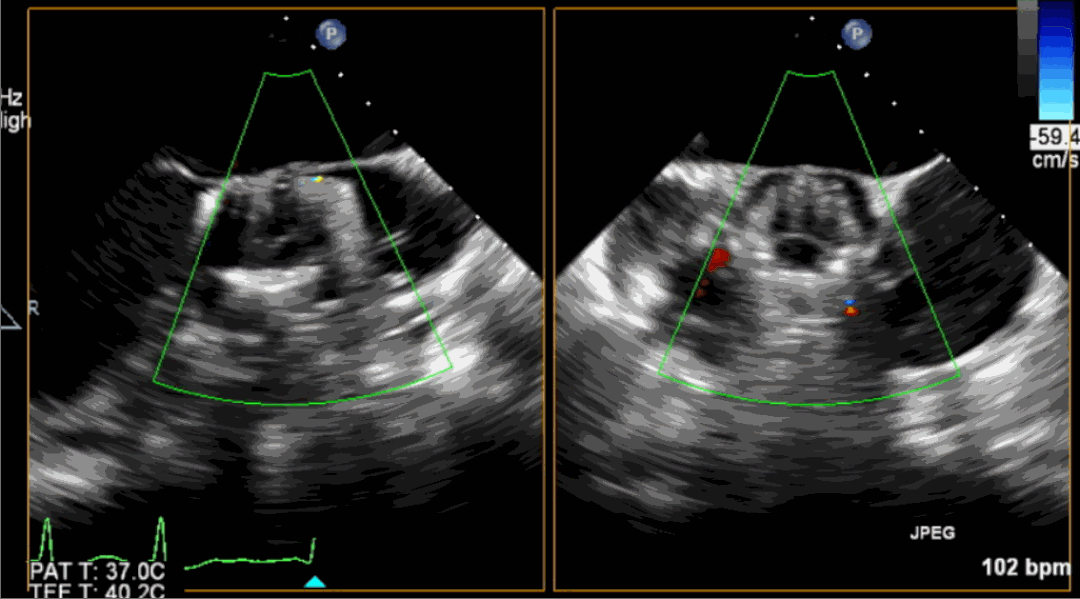

術(shù)前超聲影像圖

術(shù)后超聲影像圖

該例患者為62歲,女性,因“間歇性心悸、胸悶、氣短、胸痛1年,加重1周”之主訴入院。入院診斷:主動脈瓣重度關(guān)閉不全,二尖瓣、三尖瓣輕度關(guān)閉不全,心功能III級;冠狀動脈粥樣硬化性心臟病。行心臟超聲心動圖提示“主動脈瓣重度關(guān)閉不全;瓣口水平以下左室下壁、后下壁搏幅減低;EF值 0.30,左房、左室大、右房大小正常高限;二尖瓣、三尖瓣關(guān)閉不全;輕度肺動脈高壓(收縮壓42mmHg);主動脈硬化;左室收縮功能重度減低。經(jīng)心血管外科劉洋、楊劍教授、麻醉科陳敏教授及超聲科孟欣教授等專家團隊綜合評估,判定患者為外科手術(shù)高危患者。

手術(shù)采用經(jīng)心尖入路,對患者進行全麻后,在左側(cè)心尖處做3-4cm微創(chuàng)手術(shù)切口,在DSA及超聲引導(dǎo)下手術(shù)順利完成。從導(dǎo)入器械到完成瓣膜置入,僅耗時約10分鐘。術(shù)后即刻主動脈瓣返流程度由術(shù)前大量返流轉(zhuǎn)為消失,患者于導(dǎo)管室拔除氣管插管,次日由ICU轉(zhuǎn)入普通病房。